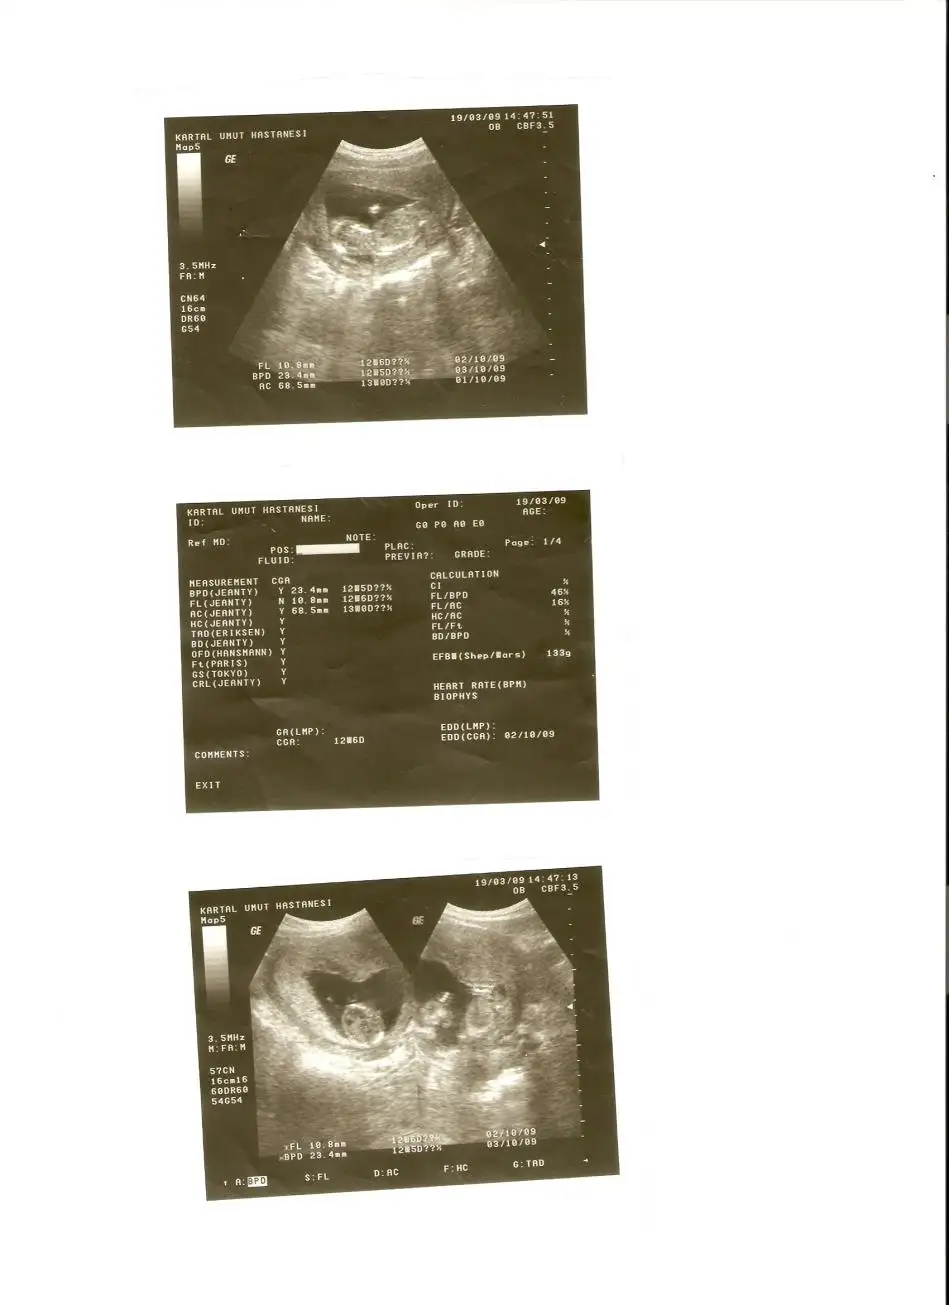

teşekürler kızlar hepiniz sağolun...bunuda başka bir hastanede çekilmiştim.hatta doktor 14 cm 133 gr diyince afallamıştım..çünkü bebek daha 13+3 tü...çok merak ediyorum bu cuma kendi doktorum ne dicekk:)

cnm 14cm ayaklarına kadar olan boyudur onun.benım doktorum FL uzunlugunu 7 ıle carparak da hesaplıoruz demıstı boyunu.senın FL=10.8 onu 7 ıle carpınca 12.6cm oluo o da normal zaten.